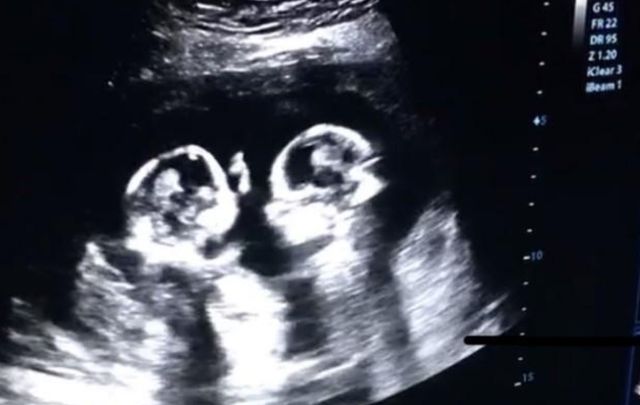

于是宝妈就来到了医院检查,也就发现了这样一幕,在医生的B超下显示,这两位双胞胎非常的不安分,它们竟然在宝妈的肚子中打起了架,是你踢我一脚,我打你一拳的,让人感到非常的滑稽。

这虽然给宝妈带来了困扰,不过宝妈在看完之后,也是感到非常的幸福,不少网友也表示:这哥俩还真挺好,从小就相依相偎的,对此,小伙伴们是如何看待的?